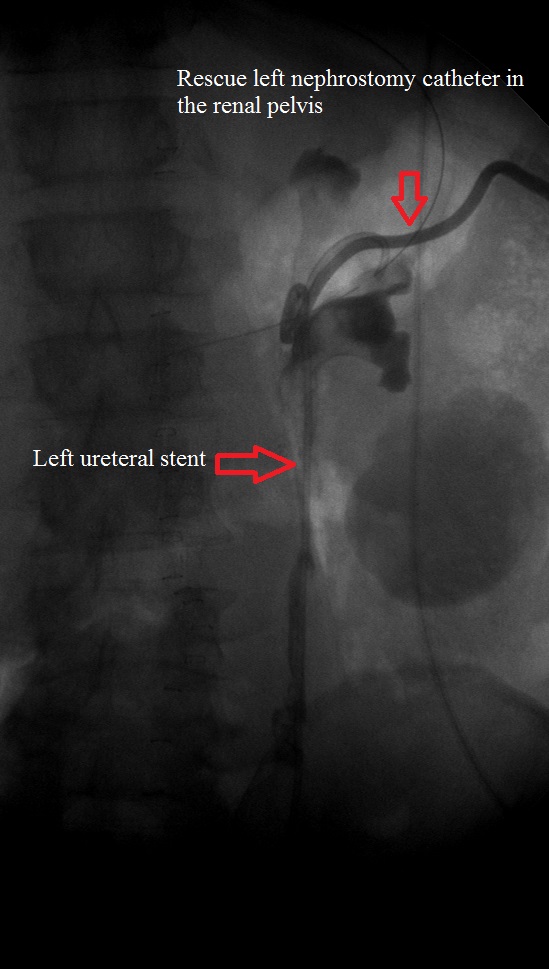

Post ureteral stenting and nephrostomy catheter insertion Medrad Clinics

Post ureteral stenting and nephrostomy catheter insertion Medrad Clinics Post Nephrostomy Tube Placement placement of a nephrostomy tube is temporary and allows urine to drain outside of your body when it can’t flow through your urinary system as normal. after nephrostomy tube placement, most patients have bloody urine for several hours; this guide provides information to clinicians on how to care for a patient with a nephrostomy tube. percutaneous. Post Nephrostomy Tube Placement.